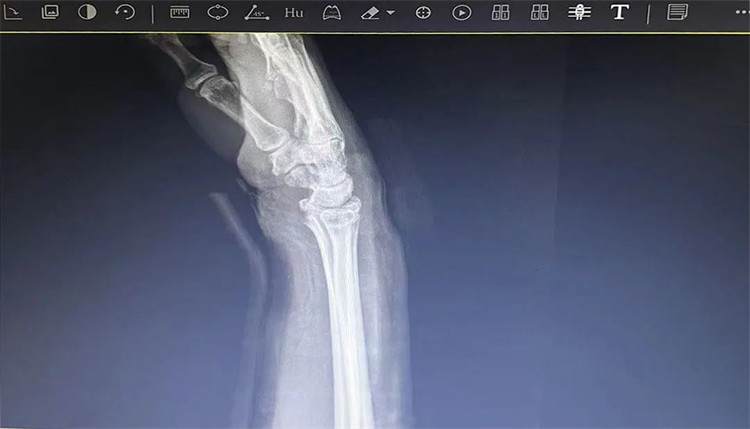

患者老年女性,50多歲,在騎電動車停下時因電動車倒下,右手著地,當即感覺,右腕及骶尾部腫痛伴右關節(jié)畸形、活動受限,急來我院就診。門診醫(yī)師結合病史、查體及輔助檢查后,診斷為:右橈尺骨遠端骨折、骶尾部挫傷并收入住院部。